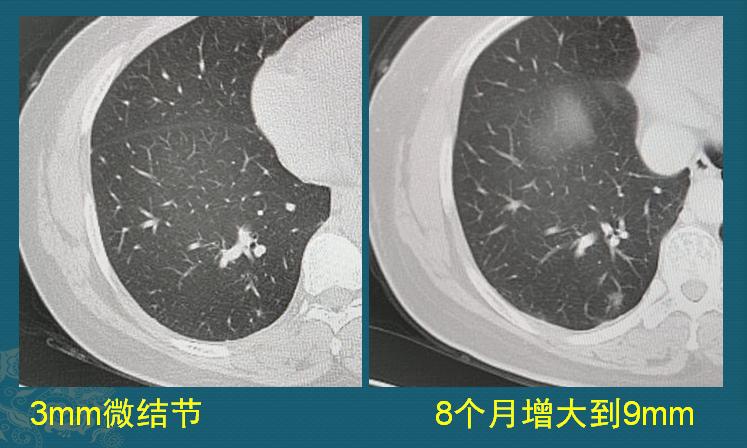

病例3,肺结节9mm,微浸润腺癌

这是一位45岁女士,体检发现3mm微结节,8个月后复查,增大到9mm,我们知道,随访增大的磨玻璃结节要列入高危结节,治疗应更积极一点,她做了胸腔镜楔形切除手术,病理是微浸润腺癌:

纯磨玻璃肺结节,大多数生长缓慢,属于惰性病灶。但确实有上图这种比较擅长短跑的结节,所以对于首次发现的肺结节,第一次复查间隔都要短一点(3-6个月),避免错过!一般一年内发现增大超过2mm的纯磨玻璃结节,多为微浸润腺癌。如下图:

本病例来自山东肿瘤医院黄勇教授

这位女士左下肺磨玻璃结节,9个月的时间增大了3mm,手术病理是微浸润腺癌,已经治愈!